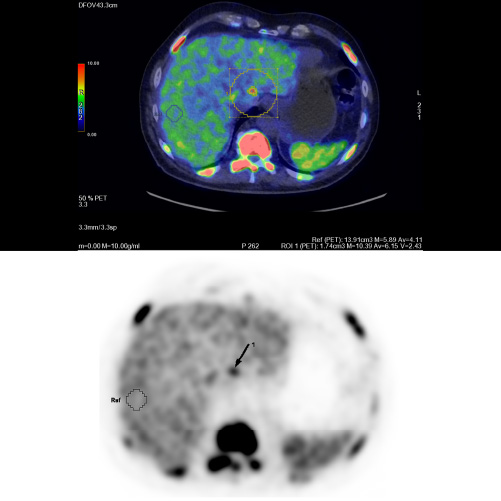

Paziente con anamnesi di malattia coronarica e pregresso impianto di stent sulla discendente anteriore sinistra.

Per prima cosa, esamina l'intera scansione. Concentrati sul tronco comune e sulla porzione prossimale della discendente anteriore sinistra.